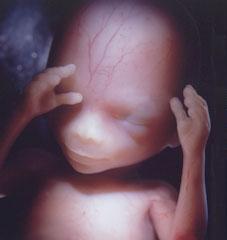

Другий триместр вагітності. 14 тиждень вагітності.

Це початок плідного періоду. У малюка добре розвинена голова. Так як нервова система все більше ускладнюється, рухи стають все більш скоординовані і явні. У малюка є ніжна прозора шкіра, під якою чітко видно кровоносні судини. На голові дитини починають рости перші волосся. Можна визначати стать дитини по крові матері.

Другий триместр вагітності. 16 тиждень вагітності.

Шкіра плоду все також тонка і прозора, але вже придбала рожевий відтінок. Відмінно видно всі частини тіла: ручки, ніжки, очі. Стало видно вушка. Малюк активно штовхається в животі мами, вже може здійснювати хапальні рухи руками, відкривати рот, моргати.

Другий триместр вагітності. 18 тиждень вагітності.

Це час зростання і розвитку раніше сформованих органів і систем. З основного можна виділити початок спроб дихання - це початковий слабкий процес, якого поки замало для нормального дихання. Шкіра плоду в даний період вагітності покрита спеціальним мастильним речовиною. Можна визначати стать дитини по УЗД.

Другий триместр вагітності. 20 тиждень вагітності.

На 20 тижні вагітності плід стає вже крихітним чоловічком з добре розвиненими пальчиками, досить скоординованими рухами. На тільце можна бачити волосся: на голові, брови, вії. У цей період вагітності добре прослуховується серцебиття за допомогою звичайнісінького стетоскопа. Зараз йде активний розвиток головного мозку.

Незважаючи на таку високу ступінь розвиненості малюка, малюк, що народився на 20 тижні вагітності, дуже мало шансів вижити і вирости здоровим.